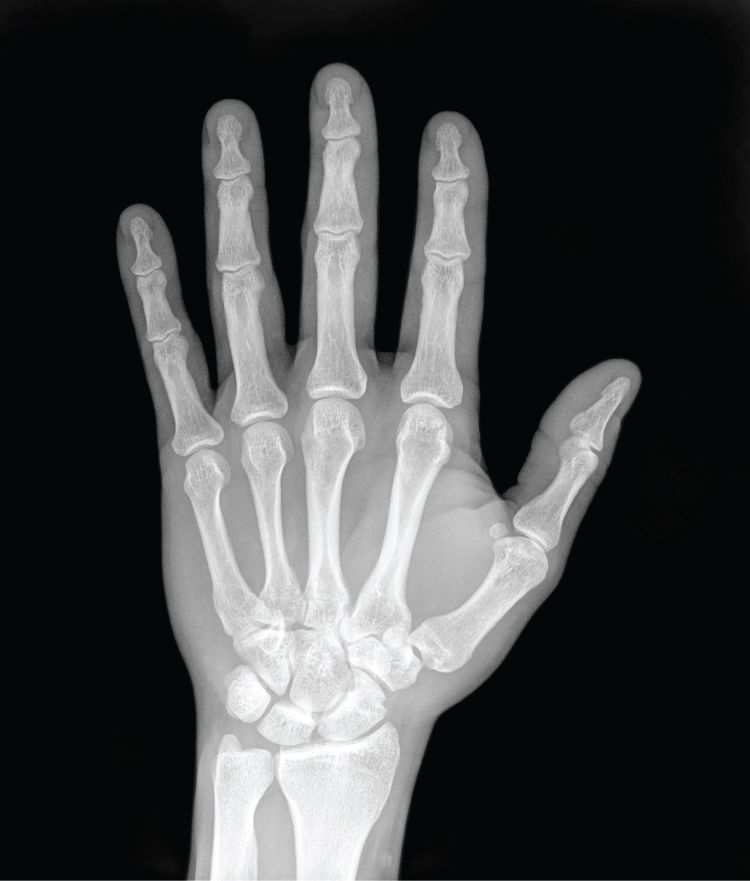

In 1895, Wilhelm Röntgen discovered X-rays—electromagnetic waves that can penetrate soft tissues but are blocked by dense structures like bone. The first X-ray image (his wife's hand) unveiled the potential of this technology. By 1900, X-rays became a standard diagnostic tool.

X-rays reveal bones and teeth with high contrast, making them ideal for fracture and dental imaging. Modern technology reduces radiation exposure and improves resolution, but repeated scans still carry risks.

X-Ray of a Hand

Figure 5.1: X-ray of a hand showing internal bone structures. (credit: Trace Meek/flickr)